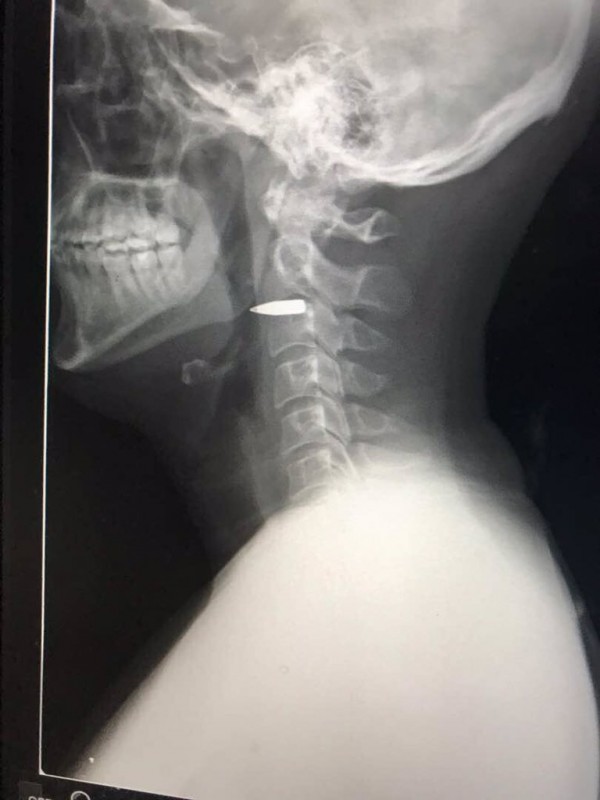

Когда же ему сделали рентген, стало очевидно, что в его шее застряла пуля. Рентгеновский снимок области шеи журналист опубликовал на своей странице в Twitter. На изображении видно, что пуля прошла между позвонков и, по заверениям репортера, не задела никакие жизненно важные точки.

Репортеру оказали медицинскую помощь, но пулю из его шеи не извлекли.

Thanks everyone - I'm okay. Bullet is still in my neck, but it missed everything important. pic.twitter.com/PBYfdrTTa6